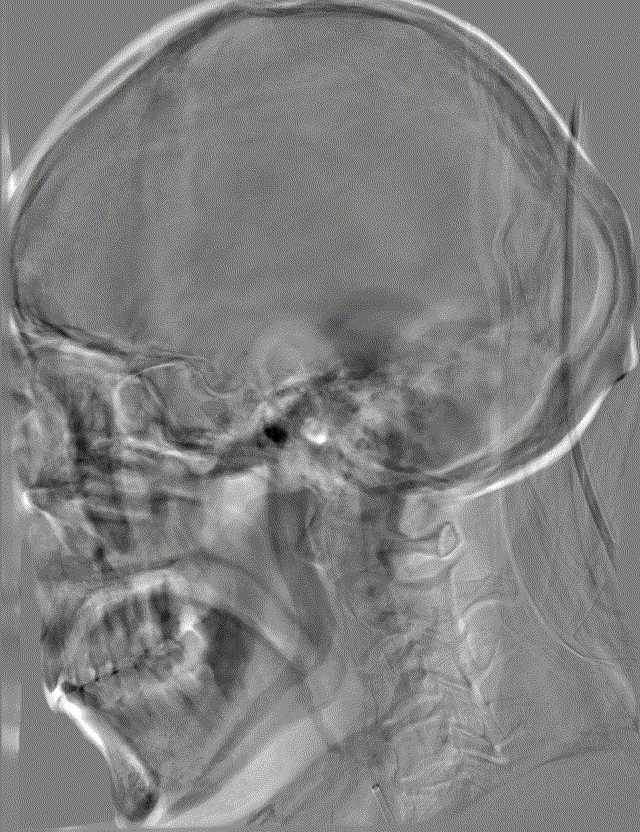

影像信息

左侧颈总动脉正侧位造影